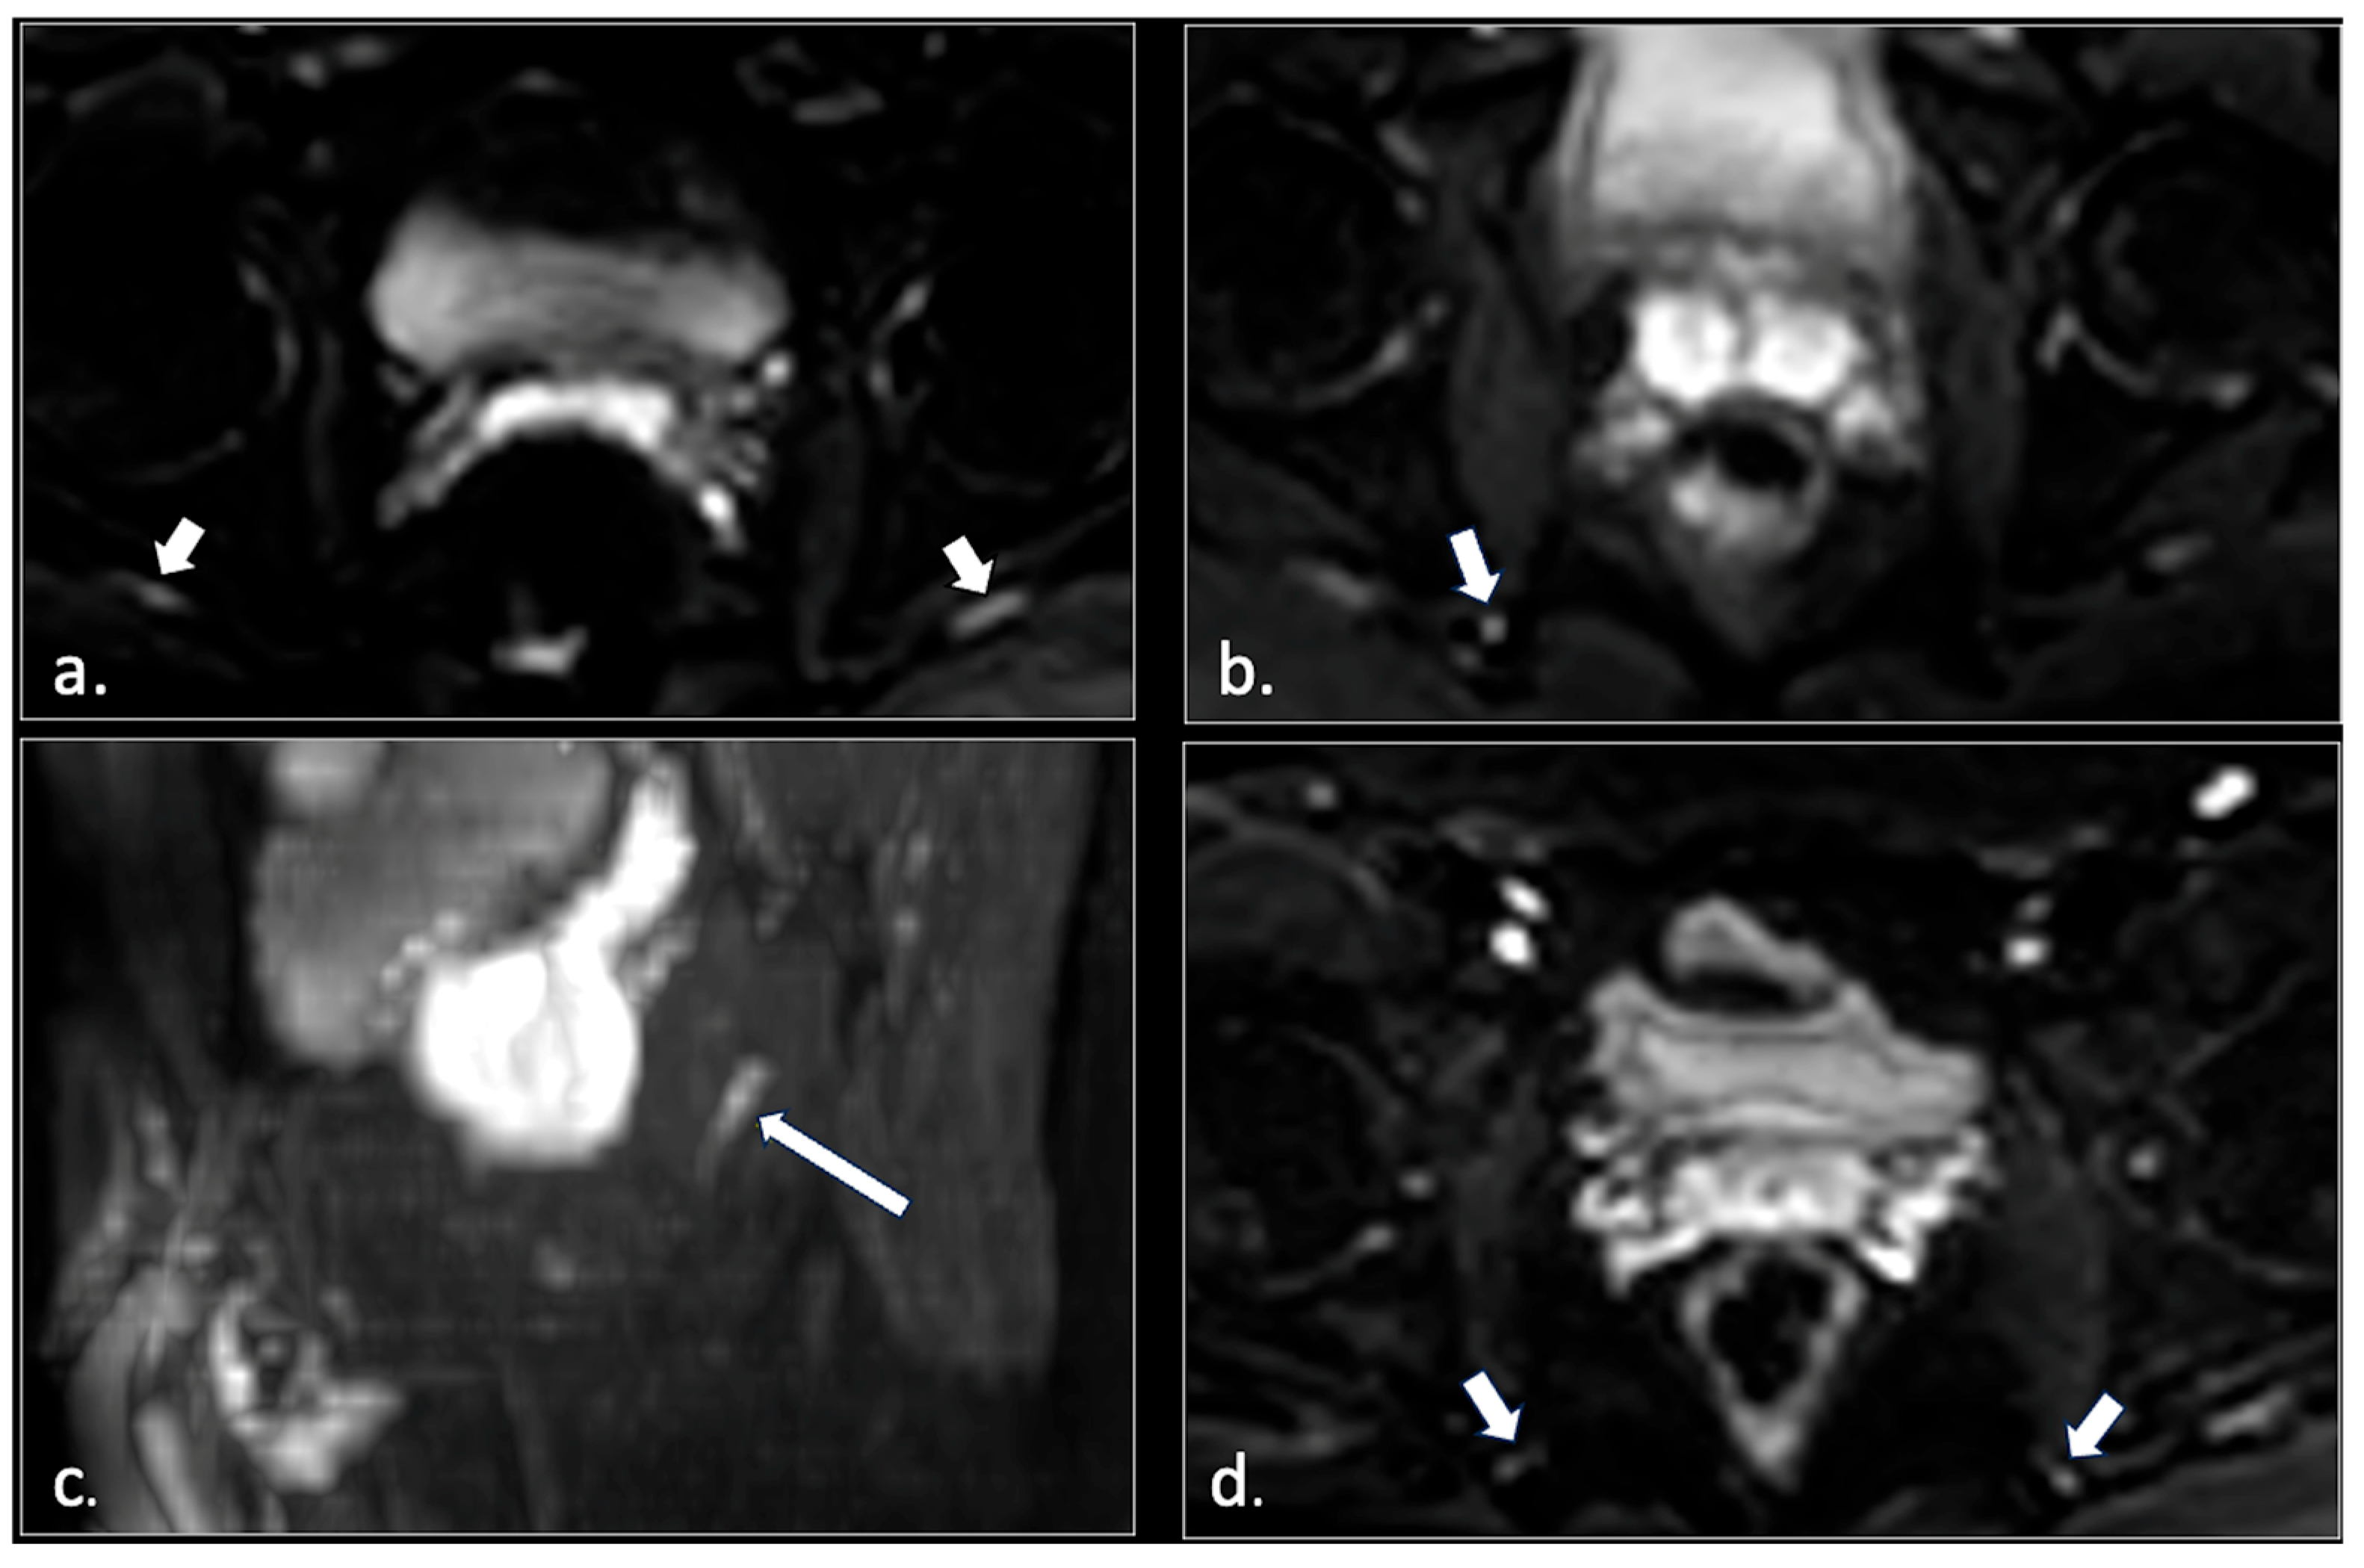

- Unilateral or bilateral hypertrophy of the pyriform muscle (4 patients);

- Unilateral or bilateral lesions of the sacrotuberous and/or sacrospinous ligaments (interligamentous space) (5 patients);

- Unilateral rupture of puborectal and/or pubococcygeal muscle (4 patients);

- Perineal fibrosis involving Alcok’s canal (4 patients);

- Pudendal nerve schwannomas (2 patients);

- Varices of the pudendal vein in the Alcock canals (2 patients).